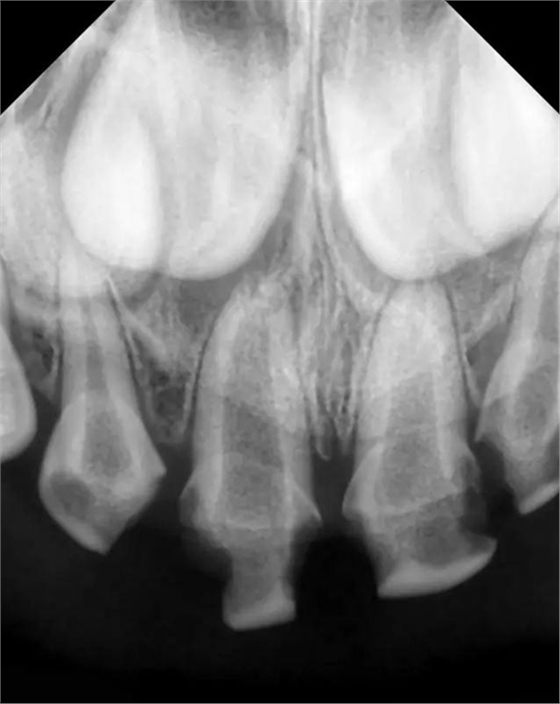

檢查:51,殘冠,牙合面齲壞達牙本質(zhì)深層,冷熱診無反應,探診(-),叩痛(+),唇側牙齦見瘺管,X線示根尖部見大面積低密度陰影;52,61,62頸部環(huán)狀齲壞達牙本質(zhì)深層,冷熱診敏感,探診(+),叩痛(-),X線示齲壞低密度陰影與髓腔連通。

診斷:51 根尖周炎

52,61,62 牙髓炎